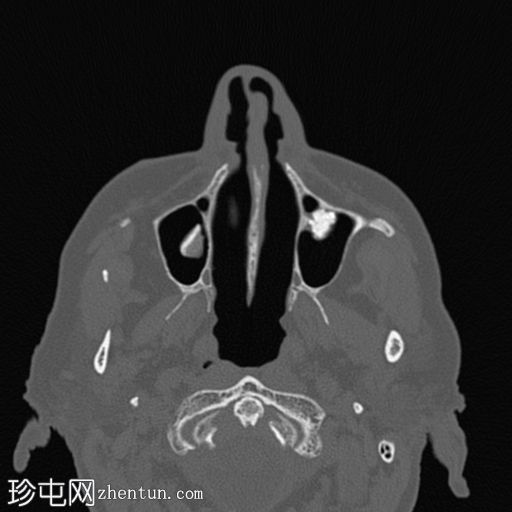

锥形束

CT

轴向骨窗

显示上颌窦左侧牙槽窝处植入了非有机牛骨移植,并植入了种植体。右侧上颌窦提升术使用骨板保留下方空间,并用自体骨填充。